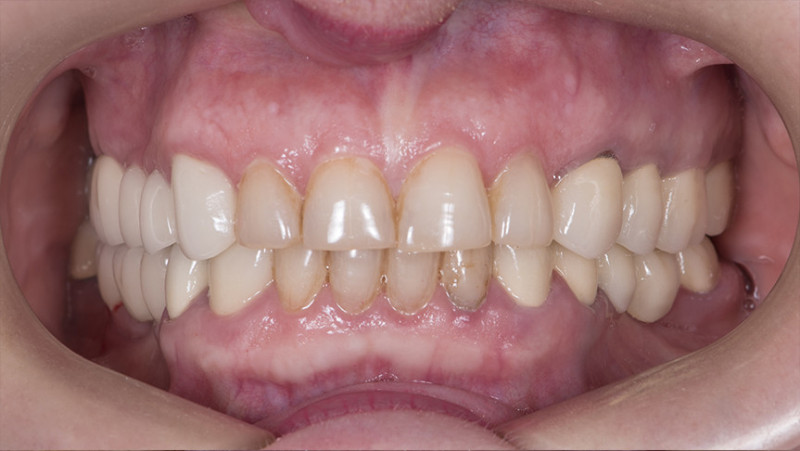

Установка коронки на зуб

Провели швейцарскую профгигиену. Перелечили зубы с несостоятельными пломбами и воспалениями. Удалили 7 зубов на верхней и нижней челюсти с одномоментной имплантацией 9 имплантатами, костной пластикой и пластикой десны. После приживления имплантатов установили временные коронки. Изготовили и установили абатменты Procera и 28 единиц керамических коронок EMAX.